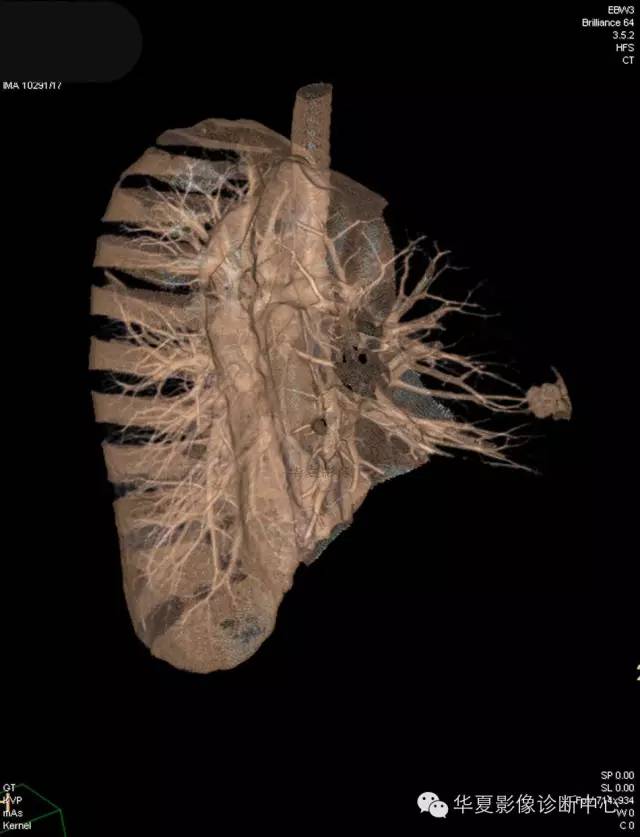

【病例学习】典型周围型肺癌CT病例一例

女,56岁,其父因肺癌去世,自觉胸部疼痛不适来诊要求拍胸片。

1.右肺上叶:肺组织1块,大小13×4×7cm。切面棕红色。2.右肺上叶肿物:灰白色组织一块,大小3×1×1.5cm。切面灰白色。3.右肺中叶结节:灰白色绿豆大组织1块。4.淋巴结:灰黑色绿豆大组织1块。

(右)肺中分化鳞状细胞癌。浸及胸膜。支气管残端切净。淋巴结未见癌转移(0/10)。